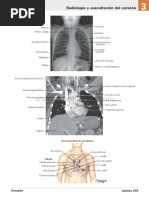

ÍTEM 1: Escribe el nombre de las estructuras del sistema respiratorio según corresponda.

Fosas Nasales

Faringe

Laringe sdsd

ssds

Bronqueo

Traquea

Alveolo

Bronqueolo

Pulmón izquierdo

Pulmón derecho

Diafrágma